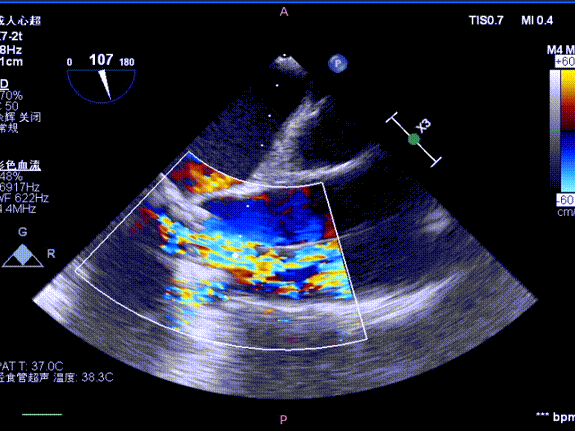

主瓣

术前

术后